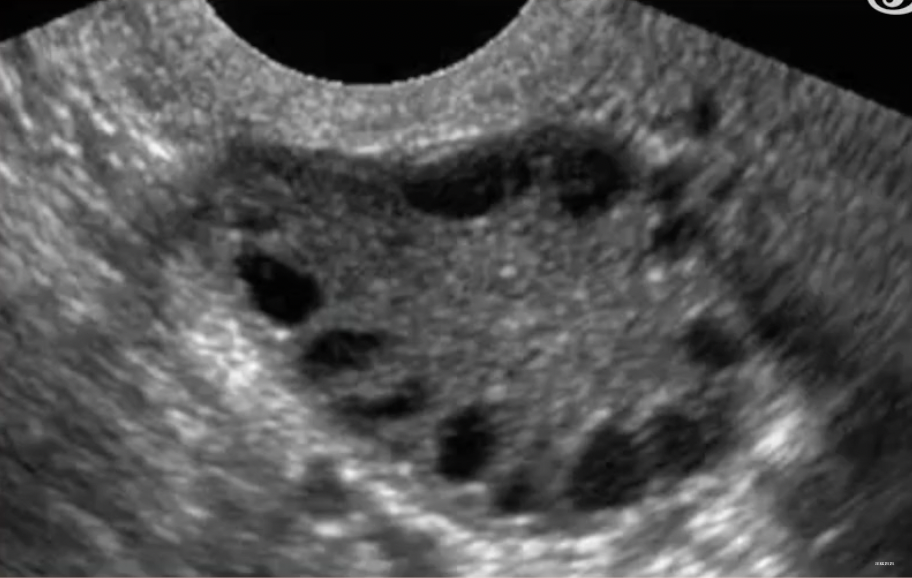

大姨妈这么简单的事情,我都做不好

多囊卵巢综合征(PCOS)的历史,最早可以追溯到阿桔初中时期。对于那些接受生理科普知识的人来说,他们知道女性的卵巢位于子宫两侧,负责释放雌性生殖激素、保护卵子,并进行排卵以供受精。然而,多囊卵巢综合征会导致卵巢内同时出现许多小卵泡,但每个卵泡只能长到2-9毫米就停止生长,无法发展成熟卵泡,也无法排出体外,由此引发一系列生理问题。

卵子长没长大我又不知道,要去医院看 B 超。”

此后每隔一段时间,阿桔都要连续几天奔赴医院,看 B 超。

∧ 阿桔的 B 超检查